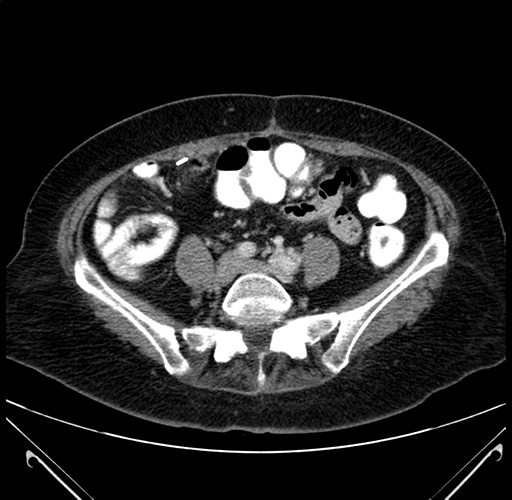

Pre-Chemo: Axial Venous